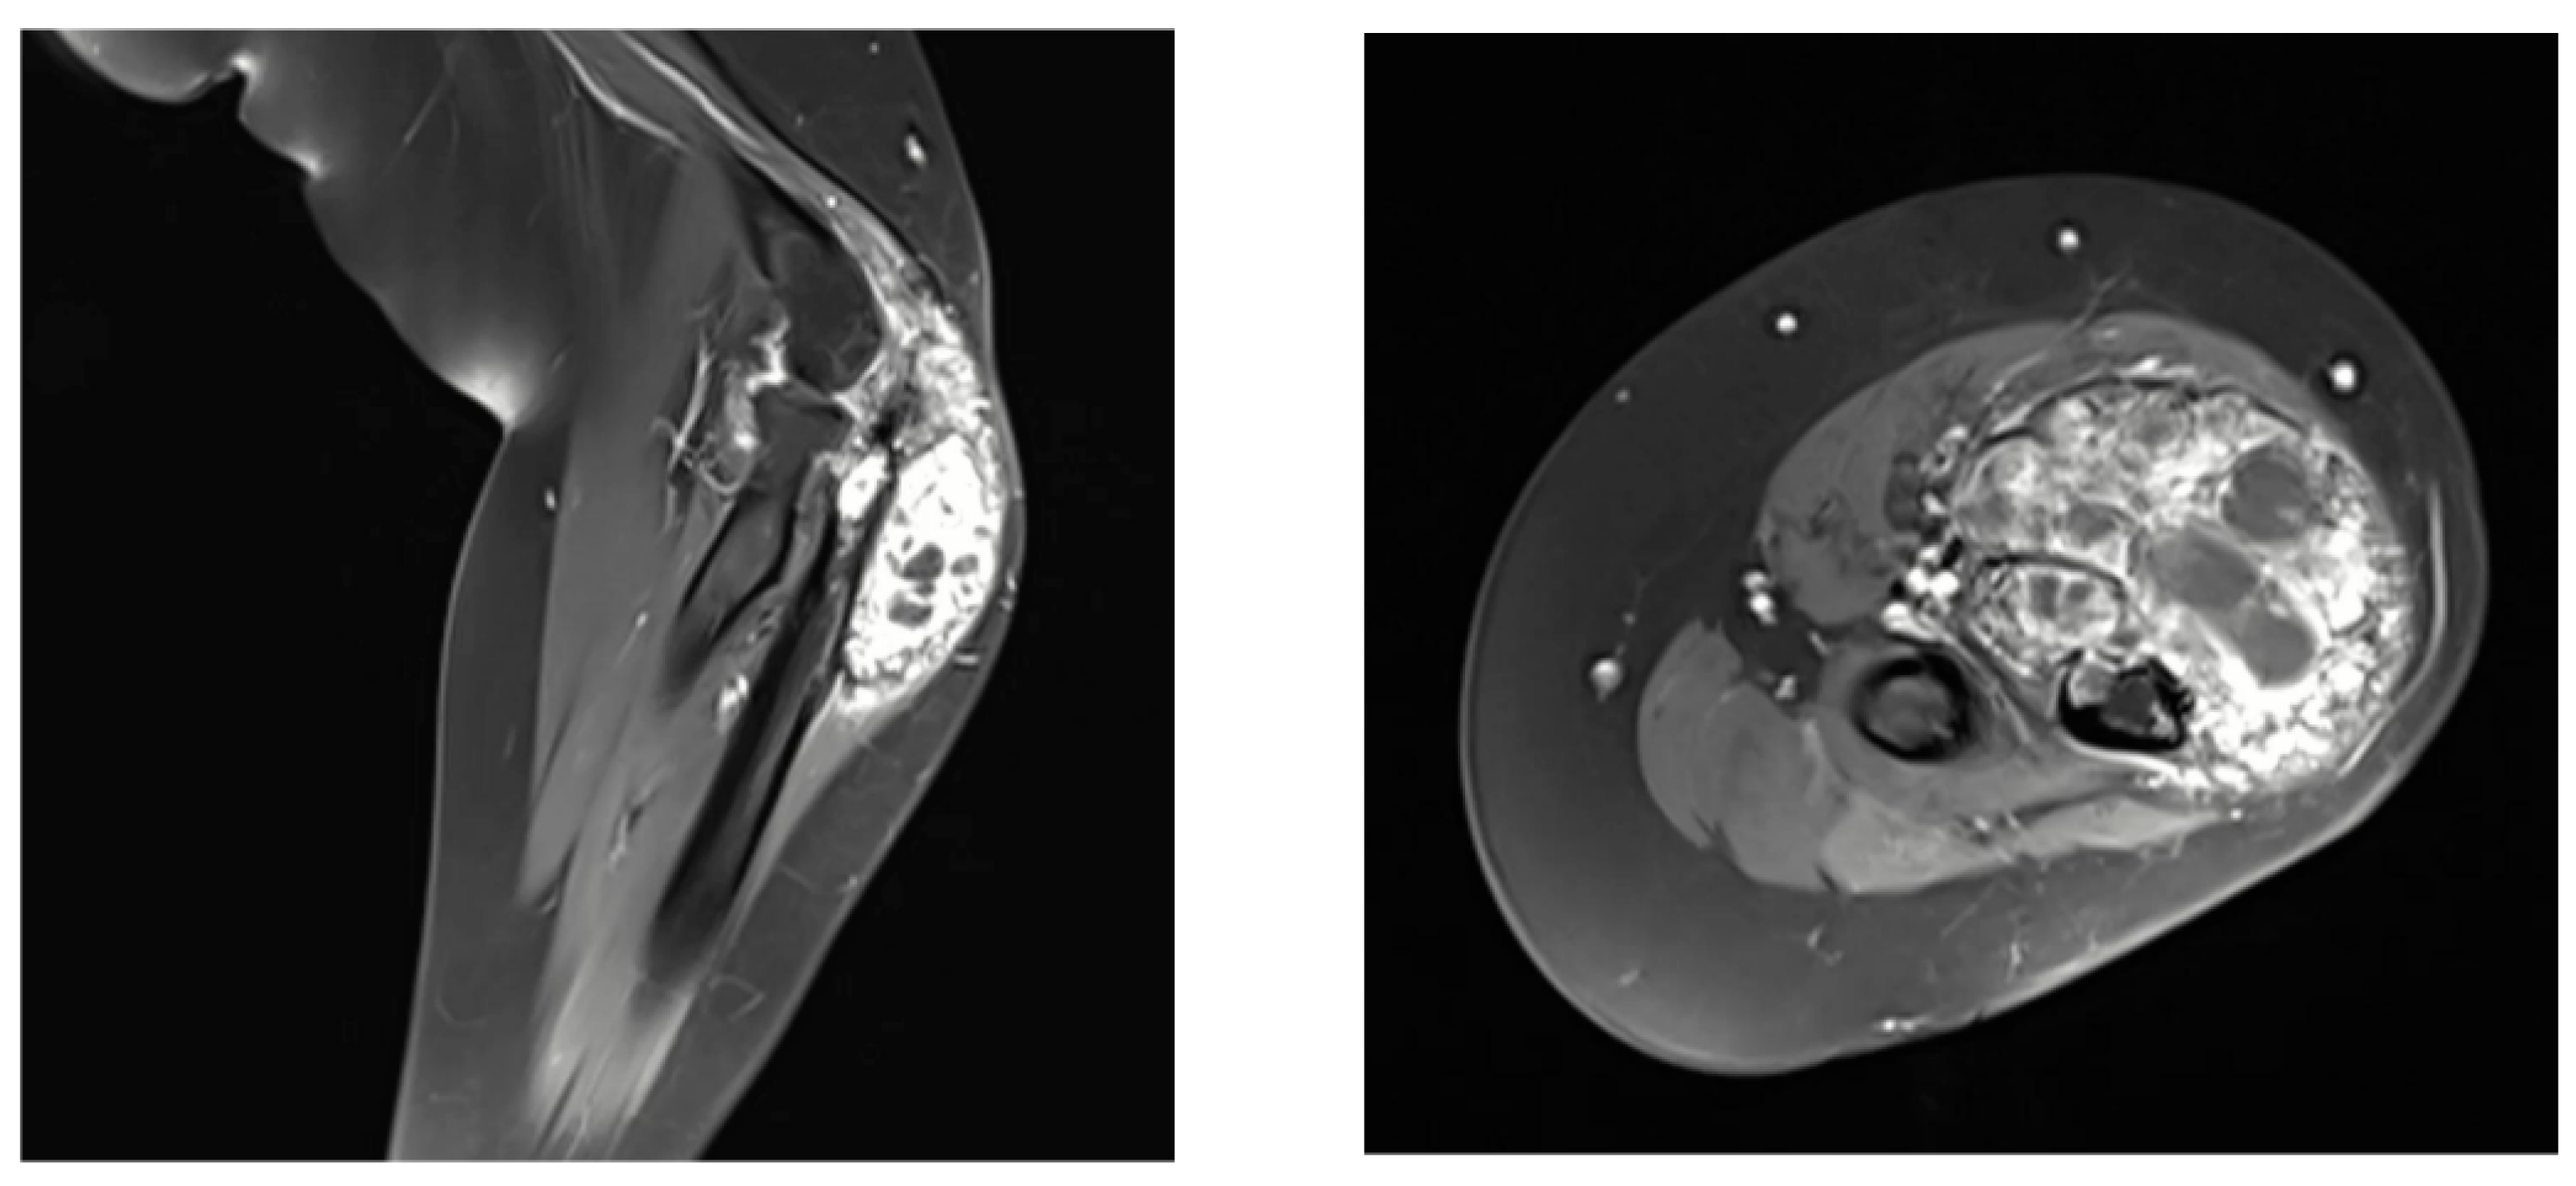

2. Case Presentation